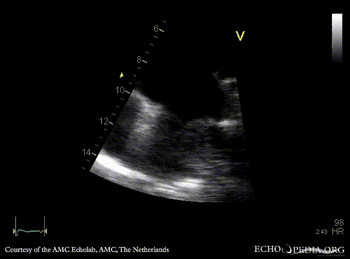

| Courtesy of: AMC Echolab, AMC, The Netherlands | |

| PSAX: tumor mass in left atrium | A4CH |

| A4CH, zoom | |